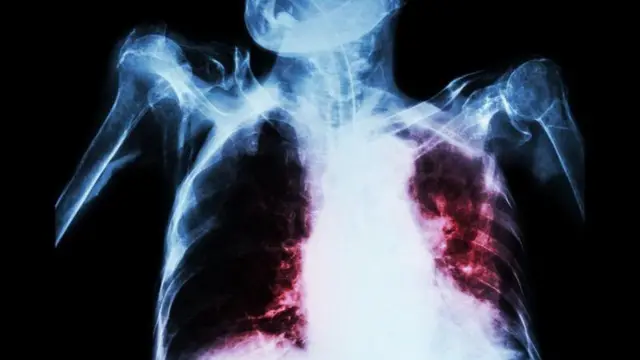

క్షయ వ్యాధి సాధారణంగా ఊపిరితిత్తులకు (pulmonary TB) సోకుతుంది. కానీ ఇది గోరు, జుట్టు తప్ప శరీరంలోని ఏ అవయవానికైనా సోకే అవకాశం ఉంది (extra pulmonary TB).

- ఊపిరితిత్తులకు సోకితే, దగ్గు, ఆయాసం, తెమడలో రక్తం పడడం కనిపిస్తుంది.